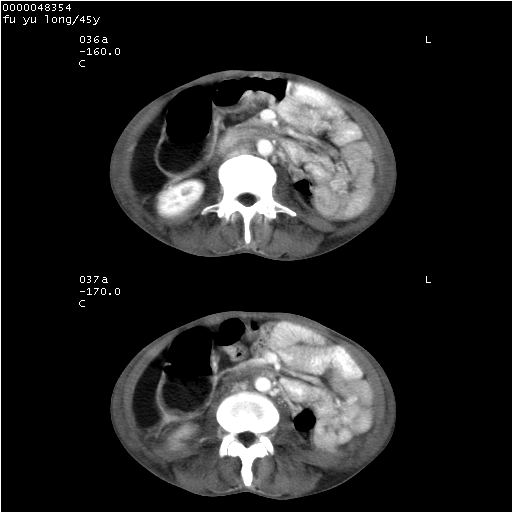

以下是引用医影拾贝在2008-5-30 2:38:00的发言:[br]气肿性胃炎、胃十二指肠溃疡、腹膜炎,考虑穿孔可能性较大

以下是引用lkc8963在2008-5-30 8:44:00的发言:[br]胃窦癌伴网膜(胃结肠韧带)/腹膜及腹膜后淋巴结转移.